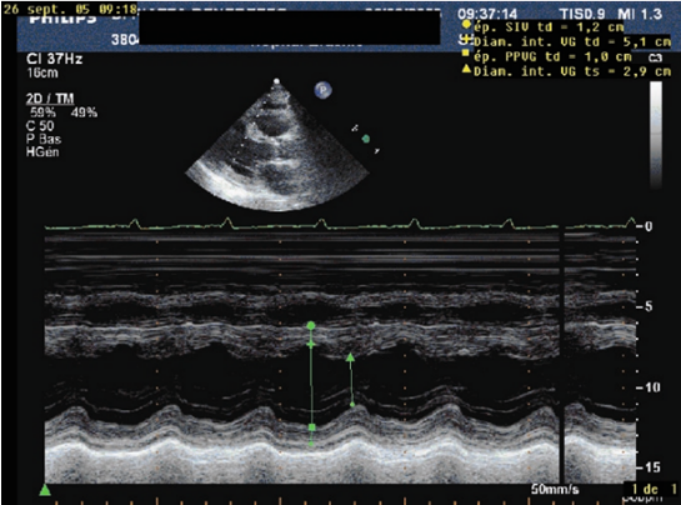

1)右房压:评估右房压时,常通过床旁超声测量下腔静脉直径及其塌陷性来估算。具体如下:需先以剑突下长轴切面为标准切面,清晰显示下腔静脉从右心房入口至肝静脉段,再借助M型超声捕捉下腔静脉随呼吸的动态变化以精准测量(图16)。测量呼气末直径(正常参考值1.5~2.5 cm,>2.5 cm提示容量过负荷),并计算塌陷率【公式:(最大直径-最小直径)/最大直径×100%】。若下腔静脉内径<1.0 cm且呼吸变化率>50%, 提示容量不足。结合下腔静脉直径与塌陷率分层判断右房压: ①当下腔静脉直径<2 cm时: 塌陷率>55%, 提示右房压为0~5 mmHg; 塌陷率30%~50%, 提示右房压为0~10 mmHg; 塌陷率<30%, 则无法估算右房压。②当下腔静脉直径>2 cm时: 塌陷率>55%, 右房压为0~10 mmHg; 塌陷率30%~50%, 右房压为10~15 mmHg; 塌陷率<30%, 右房压为10~20 mmHg。此方法利用下腔静脉呼吸变异特性, 通过超声精准测量与公式推导, 实现右房压的间接评估, 为心源性休克等场景下的容量状态、右心功能判断提供关键依据。

图片

16  M超测量下腔静脉直径